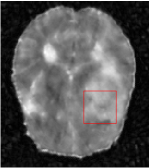

All the experiments are implemented on a Windows workstation with Intel Core i9 CPU at 3.3GHz and an Nvidia GTX-1080Ti GPU with 11GB of graphics card memory via TensorFlow Abadi et al. (2016). The parameters in the proposed network are initialized by using Xavier initialization Glorot and Bengio (2010). We trained the meta-learning network with four tasks synergistically associated with four different CS ratios: 10%, 20%, 30%, and 40%, and test the well-trained model on the testing dataset with the same masks of these four ratios. We have 300 training data for each CS ratio, which amount to total of 1200 images in the training dataset. The results for and MR reconstructions are shown in Tables 5.4 and 5.4 respectively. The associated reconstructed images are displayed in Figures 1 and 3. We also test the well-trained meta-learning model on unseen tasks with radio masks for skewed ratios: 15%, 25%, 35%, and random Cartesian masks with ratios 10%, 20%, 30% and 40%. The task-specific parameter for the unseen tasks are retrained for different masks with different sampling ratios individually with fixed task-invariant parameters . In this experiments, we only need to learn for three skewed CS ratios with radio mask and four regular CS ratios with Cartesian masks. The experimental training proceed on less data and iterations, where we performed on 100 MR images with 50 epochs. For example, for reconstructing MR images with CS ratio 15% radio mask, we fix the parameter and retrain the task-specific parameter on 100 raw data with 50 epochs, then test with renewed on our testing data set with raw measurement that sampled from radio mask with CS ratio 15%. The results associated with radio masks are shown in Table 5.4 and 5.4, Figure 2 and 4 for and images respectively. The results associated with Cartesian masks are list in Table 5.4 and reconstructed images are displayed in Figure 5.

In this section, we test the generalizability of the proposed model that tests on unseen tasks. We fix the well-trained task-invariant parameter and only train for sampling ratios 15%, 25% and 35% with radio masks and sampling ratios 10%, 20%, 30% and 40% with Cartesian masks. In this experiment, we only used 100 training data for each CS ratio and apply a total of 50 epochs. The averaged evaluation values and standard deviations are listed in Table 5.4 and 5.4 for reconstructed T1 and T2 brain images respectively that proceed with radio masks, and Table 5.4 shows the qualitative performance for reconstructed T2 brain image that applied random Cartesian sampling masks. In T1 image reconstruction results, meta-learning improved 1.6921 dB in PSNR for 15% CS ratio, 1.6608 dB for 25% CS ratio, and 0.5764 dB for 35% comparing to the conventional method, which in the tendency that the level of reconstruction quality for lower CS ratios improved more than higher CS ratios. A similar trend happens in T2 reconstruction results with different sampling masks. The qualitative comparisons are illustrated in Figure 2, 4 and 5 for T1 and T2 images tested in skewed CS ratios in radio masks, and T2 images tested in Cartesian masks with regular CS ratios respectively. In the experiments that conducted with radio masks, meta-learning is superior to conventional learning especially at CS ratio 15%, one can observe that the detailed region in red boxes keeps edges and is more close to the true image, while conventional method reconstructions are hazier and lost details in some complicated tissue. The point-wise error map also indicates that Meta-learning has the ability to suppress noises.